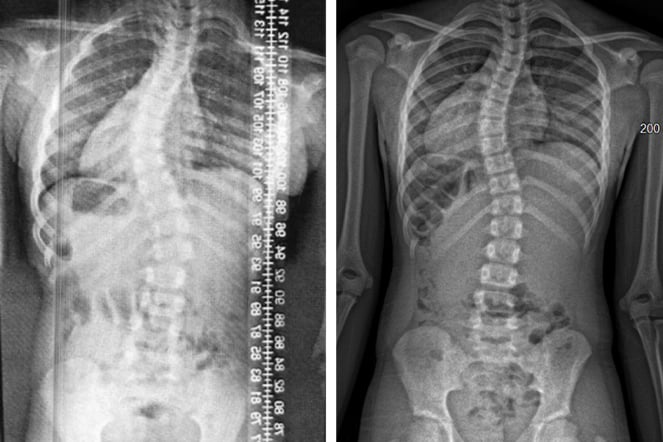

a before and after x-ray of a spine

X-rays of Savannah's spine in and out of a brace.

At Shriners Children’s Erie, Savannah and her family were met with answers. Under the care of Ozgur Dede, M.D., and Hannah Clark, MS, CPO, they learned that Savannah’s spinal curve measured 48 degrees, which is well past the 20-degree mark when bracing typically begins. “Because her curve magnitude was so severe, the team had to lay out all treatment options from the start,” said Hannah. “Bracing became the first step, with the understanding that if it was not effective, surgery might be necessary.”